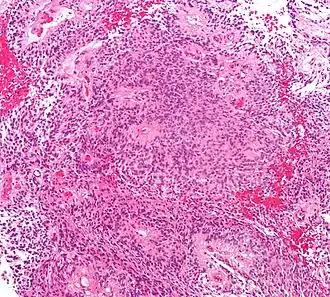

Illustrations

Radiographie d'un épendymome Archives militaires médicales

Radiographie d'un épendymome Archives militaires médicales Épendymome du ventricule 4

Épendymome du ventricule 4 Épendymome du ventricule 4

Épendymome du ventricule 4 Épendymome du ventricule 4. (à droite avec contraste augmenté)

Épendymome du ventricule 4. (à droite avec contraste augmenté)